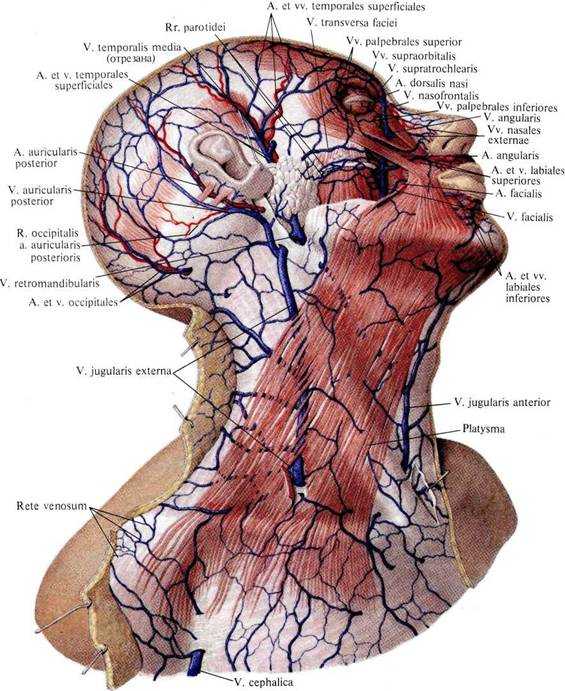

Анатомия внутренней яремной вены: КТ изображения